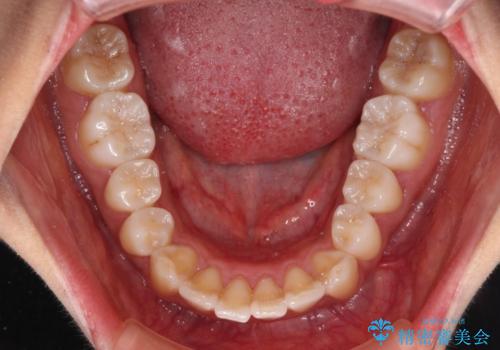

- 全体的な歯列の叢生を気にして来院された患者様です。

奥歯の咬み合わせを見ると、片方は上顎が下顎に対して相対的に前方にある状態でした。

咬み合わせを改善するためには、上顎臼歯を後方に移動させた咬み合わせにする必要があります。

インビザライン単体で改善することも可能ですが、ディープバイトのためインビザライン単体で達成する可能性が低いと考えられたため、カリエール・ディスタライザーという補助装置を併用して、より確実性を上げることとしました。

奥歯の咬み合わせ改善後に、インビザラインにて歯列を整えることとしました。